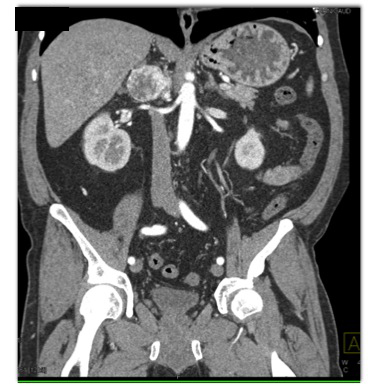

The best diagnosis in this case is

adrenal pheochromocytoma

adrenal carcinoma

adrenal adenoma

hemangioma of the adrenal